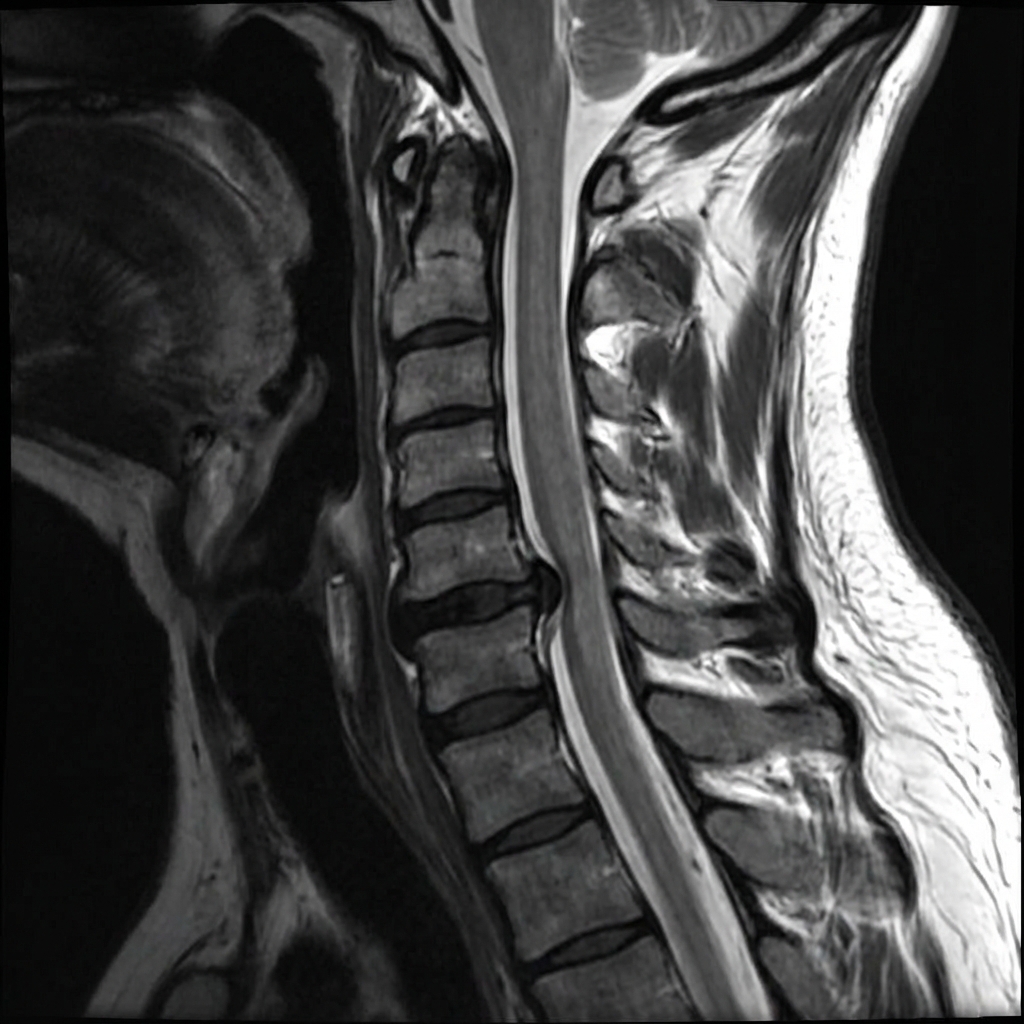

Sagittal and axial T2-weighted MRI demonstrating left posterolateral disc herniation at C6-7 with compression of the left C7 nerve root in the neural foramen. There is loss of disc height and disc signal at C6-7. The cord signal is normal. This represents cervical radiculopathy from disc herniation with concordant clinical findings.

Describe the MRI findings and correlate with the clinical presentation.